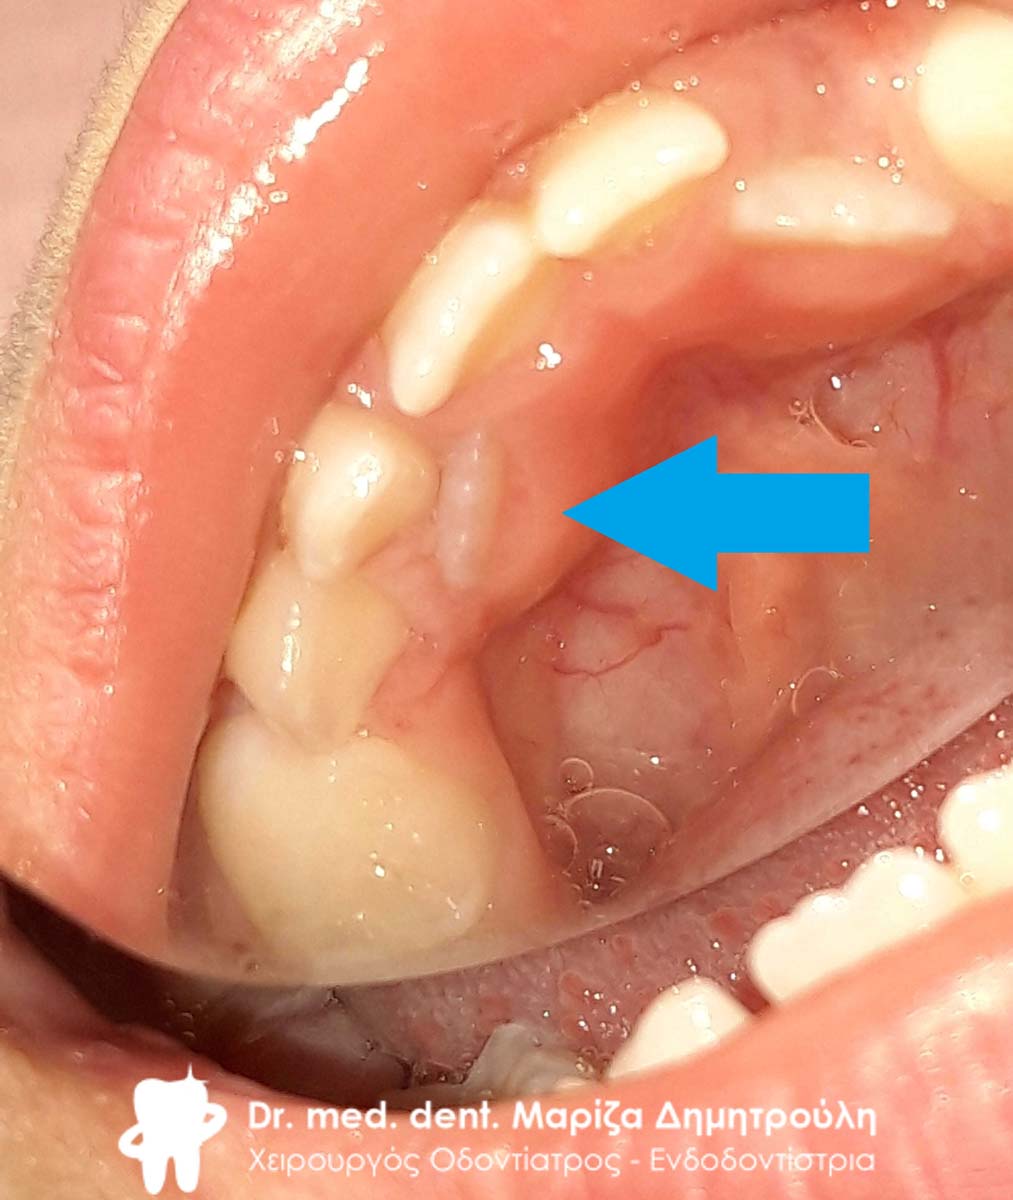

Στο συγκεκριμένο περιστατικό που παρουσιάζεται ο νεογιλός κυνόδοντας παρέμενε στη θέση του, ενώ ταυτόχρονα είχε ανατείλει ο μόνιμος κυνόδοντας. Μετά την αναγκαία εξαγωγή του νεογιλού δοντιού διαπιστώθηκε οτι δεν υπήρξε καμία φυσιολογική απορρόφηση της ρίζας του δοντιού με αποτέλεσμα το δόντι να παραμένει παραπάνω από το φυσιολογικό στο στόμα. Μετά την αφαίρεση του δοντιού ο μόνιμος κυνόδοντας πήρε την τελική φυσιολογική θέση σε διάρκεια ενός μηνός.